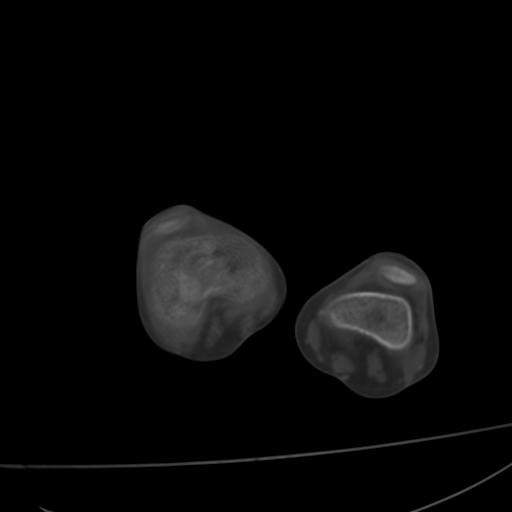

标题: PED0940:M12Y,左股骨下端酸痛畸形 [打印本页]

标题: PED0940:M12Y,左股骨下端酸痛畸形

12岁男孩,左膝关节肿痛8年,近月明显

内生骨软骨瘤?

血友性关节病?